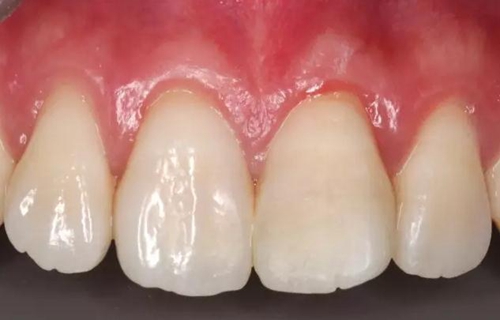

術(shù)后即刻口內(nèi)照

1個(gè)月后患者復(fù)診

口內(nèi)照顯示口腔衛(wèi)生狀況不佳,21牙面呈亞光狀態(tài),齦緣輕度紅腫。

給予健康教育,囑保持口腔衛(wèi)生。再次拋光。

患者1個(gè)半月后復(fù)診,口腔衛(wèi)生狀況保持良好,牙齦健康,折斷線不可見。